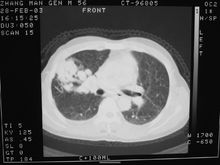

胸部PNB用以診斷肺臟、縱隔和胸壁病變,對肺內球形病籵及縱隔包塊的定性診斷有重要意義,準確率可達85%。較常見的併發症為氣胸、出血、但用細針的併發症甚少,腹部PNB套用較多,肝、膽、胰、脾、腎及腹後壁包塊均可,診斷準備性亦高;骨骼穿刺須用較粗骨穿針,可診斷骨腫瘤。此外還用於穿刺甲狀腺腫塊,眶內腫塊等等。